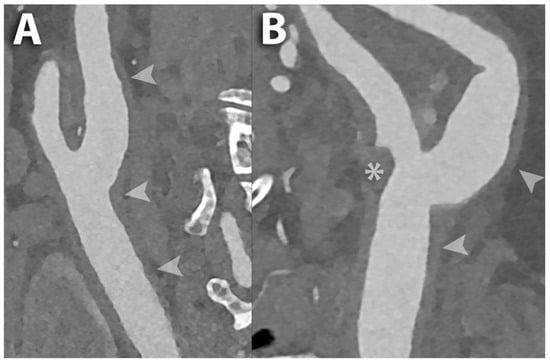

- Keser, Z.; Diehn, F.E.; Lanzino, G. Photon-Counting Detector CT Angiography in Cervical Artery Dissection. Stroke 2024, 55, e48–e49. [Google Scholar] [CrossRef] [PubMed]